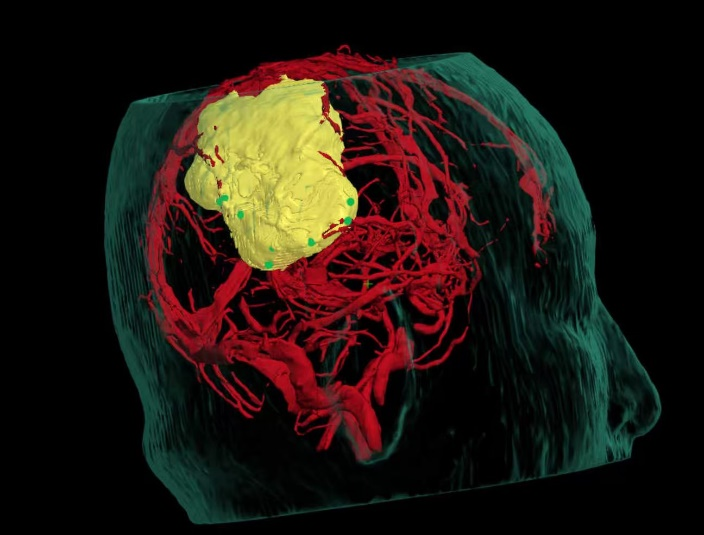

术前精准建模:运用3D Slicer软件整合多模态影像数据重建三维模型,清晰呈现肿瘤与周边功能区、血管的空间关系,为手术规划提供精准数字化依据。

术中实时导航:神经导航系统全程启用,精准匹配术前数据与术中体位,实时定位手术器械位置,成功避开关键功能区及血管,保障操作安全。